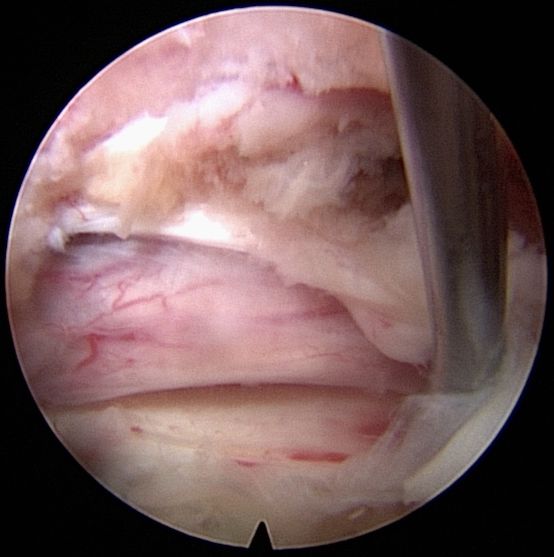

Πλάγια προσπέλαση

Πρόκειται για μια ακόμα πιο ειδική μέθοδο, κατά την οποία εισερχόμαστε μέσω του μεσοσπονδύλιου τρήματος και αποκτούμε πρόσβαση κατευθείαν στην δισκοκήλη χωρίς να χρειάζεται αφαίρεση οστικού τμήματος. Αποτελεί την λιγότερο επεμβατική μέθοδο όλων στην σπονδυλική στήλη, αφού χρησιμοποιεί φυσικά τρήματα για την είσοδο στον σπονδ. σωλήνα.